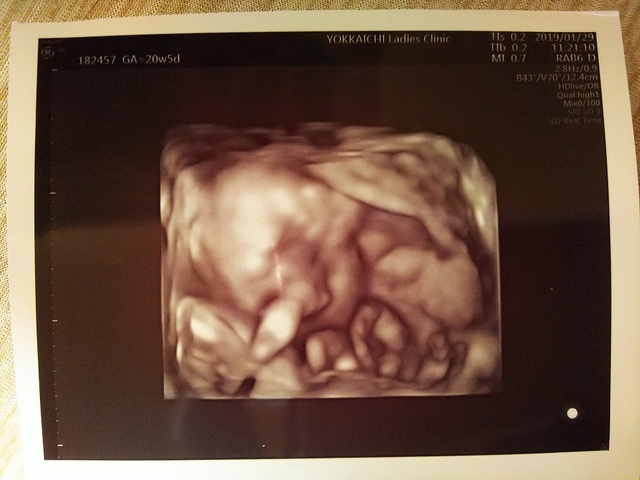

20週5日(20w5d)のエコー写真

20週5日(20w5d・男の子)|あーじゅん さん(28歳)

エコー写真撮影時のエピソード:

初めて旦那さんも一緒に健診へ行きました。エコーの画面で赤ちゃんを見ながら夫はすごく興奮していました。この時に初めて性別が分かってさらに興奮。

3D画像へ切り替えて顔を見たかったのですが、赤ちゃんの両手が顔の前にあってちゃんと見られなかったのが少し残念でした。

でも、元気に動いていて体の大きさも大きくなっていて成長しているのが分かってとてもうれしかったです。